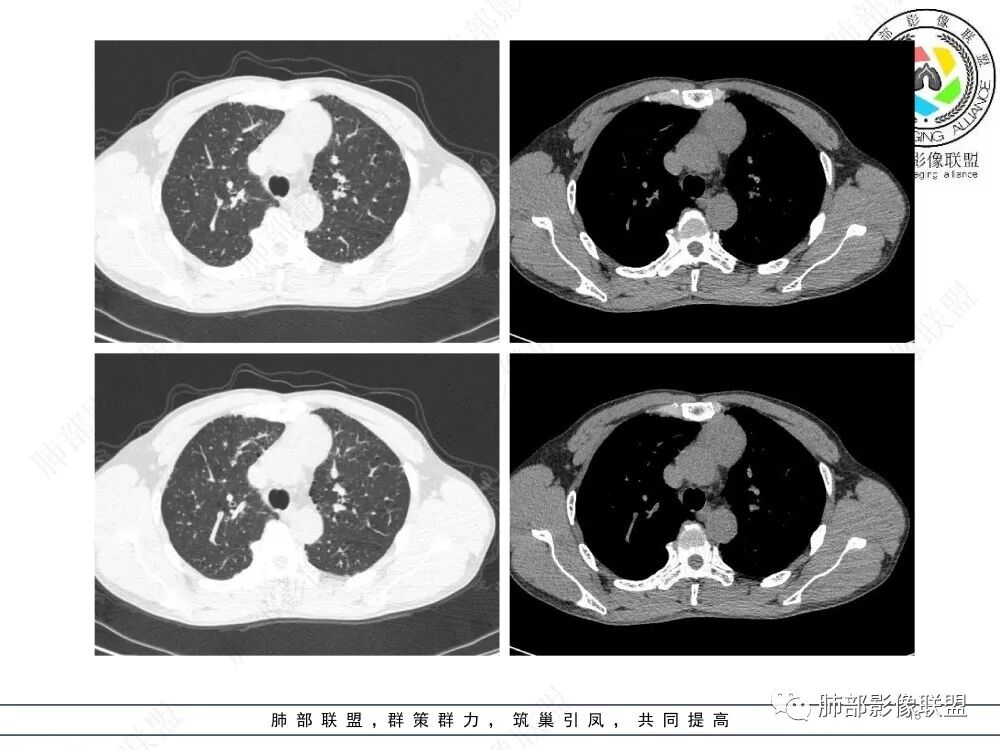

流心明智:男,47,咳嗽、咳痰1年余。胸部CT:前纵膈偏左类圆形肿块,瘤肺界面清晰光整,纵隔侧部分层面絮状影?平扫密度较均匀,增强后轻度强化,内可见宽带及线样低密度分隔。邻近左上肺受压凹陷。考虑胸腺肿瘤,AB型?胸腺Ca?鉴别淋巴瘤、N源性肿瘤、CD等。

南边:支持前纵隔、胸腺瘤首选,晨读其实定位上还是有点难度,定性常规还是考虑胸腺瘤,其他的几率比较低一些,需要鉴别的是胸膜SFT,神经源性,可惜的是没重建,一直在犹豫胸膜来源的可能性。

2、影像特点:前纵隔偏左侧软组织影,密度相对均匀,未见明显包膜钙化及实质内钙化,局部边缘浅分叶,周围脂肪间隙密度增高、浑浊,未见侵犯大血管、未见纵隔内淋巴结转移、未见侵犯心包内结构、未见胸膜转移结节、未见肿块沿着纵隔胸膜蔓延,未见胸腔积液。增强后动脉期不均匀强化,未见明显纤维分隔。

3、 病 例 小 结:40岁以上,前纵隔偏侧性生长的肿块,常规考虑胸腺瘤。难点就在于胸腺瘤的分型。但是对于前纵隔占位影像诊断的关键在于区分胸腺囊肿、胸腺瘤、胸腺癌及其他恶性肿瘤。至于胸腺瘤,主要在于判断有无侵袭性。